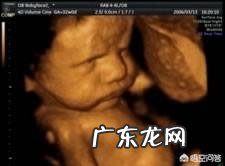

怀孕8个月时,胎儿是怎么样的?怀孕8个月,属于孕晚期,是胎儿体重猛涨期,胎儿的发育速度非常快,孕妇会随之出现一些不良的反应 。

文章插图

怀孕8个月,胎儿长约41-44厘米,重约1500-1800克,胎儿的体重增加非常快,看起来越来越丰满了,身上的胎毛也开始脱落了,长出了一些头发,指甲也成型了,皮肤有些发红,看起来还挺可爱的 。胎儿的胎动越来越厉害了,经常会踹的孕妇肚子疼,不过只要胎动有节奏、有规律,就不需要担心,孕妇可以经常跟胎儿互动 。